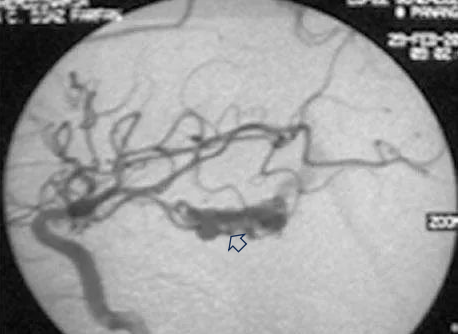

首次手术仅仅三个月后,大卫在学校突然昏迷,紧急送往医院后,检查为左侧颞角的脑动静脉畸形导致脑室内出血(图a、b)。

图(a)左侧 ICA 造影,侧位和 lPChA